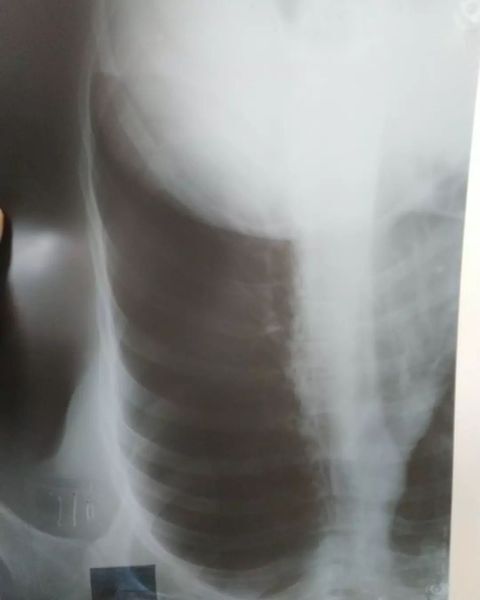

Михаил Соломонов: «Шестидесятикилометровое велопутешествие Волжский путь прошло отлично, не считая сломанных у меня двух ребер. Положили в больницу. Всем мир!»

Михаил Соломонов: «У меня уже всё хорошо! Вчера сделали операцию и сегодня из травмы перевели в хирургию с пневматораксом. Оказалось, что сломанные ребра разорвали лёгкое и воздух заполнил грудную клетку. Врач Алик Ренатович со своими помощницами пробили мне лёгкое и поставили катетер с лёгочной жидкостью. Иду на поправку».